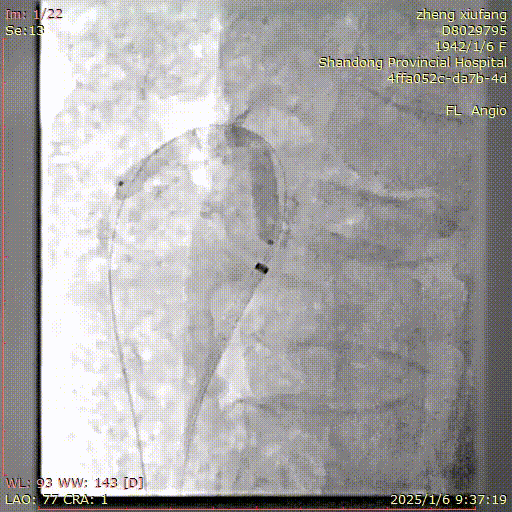

患者取仰卧位,常规消毒铺巾,1%利多卡因局麻后,逆行穿刺右侧股动脉,置入6F血管鞘,泥鳅导丝配合猪尾导管送至胸12水平,正位及侧位造影见肠系膜上动脉起始部钙化严重,可见支架影,支架内重度狭窄,肠系膜上动脉中远段延迟显影。经右股动脉入路更换7F 55cm RDC长鞘,导丝、导管配合选入肠系膜上动脉并通过病变段,建立轨道。沿导丝送入4mm球囊扩张病变段,扩张后造影见肠系膜上动脉支架内狭窄较前有所改善。再沿导丝送入7mm✖60mm震波球囊,扩张后再次造影示:肠系膜上动脉显影较前明显改善,支架内造影剂通过顺利,未见明显残余狭窄,无造影剂外溢,遂决定结束手术,缝合器缝合穿刺点,无菌敷料加压包扎,手术过程顺利,术后患者安返病房。

建立入路

4mm球囊预扩

处理前造影